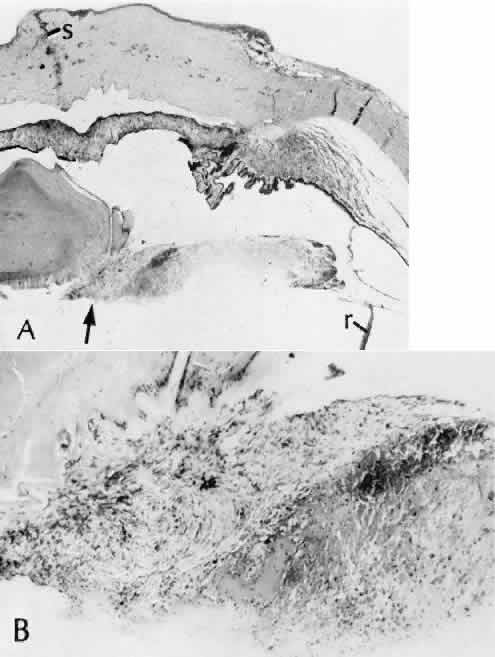

Wound healing of the neurosensory retina follows the principles of wound healing. There is an initial removal of all necrotic tissue by phagocytosis followed by proliferation of cells to form a chorioretinal bond. The healing, however, is modified in most instances by the lack of participation by the blood vessels.43–45 Astrocytes from the neurosensory retinaproliferate from the peripheral viable tissue into the wound and downward into the area of the subretinal space (Fig. 12). Retinal pigment epithelial cells from the peripheral viable tissue undergo fibrous metaplasia and proliferate upward into the area of the subretinal space. When the two proliferating cell types unite, a tight chorioretinal bond is formed. Increased retinal adhesiveness has been estimated to be 140% of the normal degree of adhesiveness 2 weeks after photocoagulation.46 Retinal holes may heal spontaneously if supported by an intact vitreous base or if located adjacent to the retinal pigment epithelium (Fig. 13).47,48 For the retinal pigment epithelium to differentiate, it must be in contact with overlying retinal pigment epithelium.49 Choriocapillaris repair from a photocoagulation wound of the retina appears to proceed in a manner similar to that of repair of capillary thrombosis in other tissues.50 The vascular repair process may not reproduce the lobular architecture of the native choriocapillaris.51 The choriocapillaris may regenerate in areas of restored retinal pigment epithelium.52 Proliferative vitreoretinopathy is an expression of abnormal retinal wound healing.53

Fig. 12. Light micrograph of an area over a retinal buckling element for retinal reattachment. Cryotherapy has been applied in the area, causing atrophy of the neurosensory elements of the retina. There is an intimate association of the remaining glial elements of the retina (R) with proliferated retinal pigment epithelial cells in the plane of the former subretinal space (arrow). The adhesion prevents intraretinal separation in this area. (Periodic acid-Schiff stain; × 100.)

Fig. 13. Retinal healing by proliferation of glial cells. In the presence of an intact vitreoretinal interface acting as a scaffolding, retinal glial cells are able to proliferate and seal small retinal holes. The arrow indicates artifactually detached vitreoretinal interface.